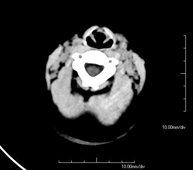

- TC Cráneo

Prueba radiológica que consiste en obtener imágenes del cráneo de alta definición anatómica (tronco cerebral, cerebelo, cerebro, calota craneal, etc.), mediante el empleo de un equipo de TC (Tomografía Computarizada).Indicaciones: traumatismos, cefalea, trastornos de la memoria, pérdida de fuerza súbita en una extremidad o mitad del cuerpo. - TC Cuello